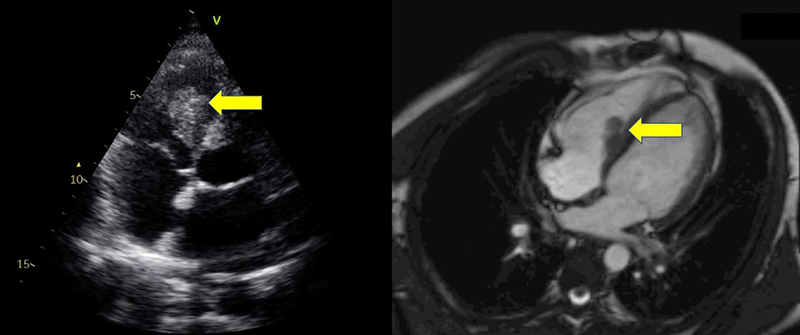

Transthoracic echocardiography revealed preserved left ventricular systolic function, but identified an echodense, heterogeneous mass in the right ventricular cavity (figure 1). Cardiac magnetic resonance imaging (MRI) provided further characterisation of this finding, demonstrating a non-enhancing, avascular mass with low signal intensity on both T1- and T2-weighted sequences, and absence of perfusion or late gadolinium enhancement — features consistent with thrombus (figure 1). Chest computed tomography (CT) revealed bilateral pulmonary nodules with a vascular distribution, suggestive of embolic events. Positron emission tomography (PET) showed vascular hypermetabolism in the left lower limb and pulmonary hila, consistent with vasculitis.